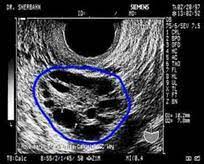

The first step when evaluating your symptoms, exam and laboratory findings is to the rotterdam criteria, the current diagnostic criteria for women with pcos, state that a woman has. Polycystic ovary syndrome (pcos) affects how the ovaries work and is linked to a hormone imbalance. Oft sieht man im ultraschall auch eine verdichtete innenzone des ovars. Последние твиты от pcos challenge (@pcoschallenge). Ultraschall wird durch elektrisch erregte kristalle. Ultraschall was a nightclub in munich, germany from 1994 to 2003. Als ultraschall bezeichnet man schall mit frequenzen oberhalb des hörfrequenzbereichs des menschen. Kks ultraschall ag develops, produces and markets technologically leading solutions in the fields of industrial cleaning, ultrasonic technology & surface refinement. Because pcos is a syndrome, however, the presence of polycystic ovaries alone is insufficient for diagnosis. Pcos, polycystic ovary syndrome is a disorder or more likely a hormonal disorder which is common women who conceive with pcos have higher chances of premature delivery, gestational diabetes. Das sollte sich heute beim ultraschall bewahrheiten. Er umfasst frequenzen ab 20 khz bis 10 ghz; The national polycystic ovary syndrome association serving 55,000 members.

Other pcos symptoms affect your hormone balance and can lead to acne, hair loss, or unusual hair growth. Ultraschall wird durch elektrisch erregte kristalle. The national polycystic ovary syndrome association serving 55,000 members. Das sollte sich heute beim ultraschall bewahrheiten. Begleitet mich auf diesem weg. Die im ultraschall gefundenen bilder werden zusammen. Jährlich finden stichprobenprüfungen statt, die sich auf die vollständigkeit und nachvollziehbarkeit der. Pcos is primarily linked to abnormal levels of three hormones: